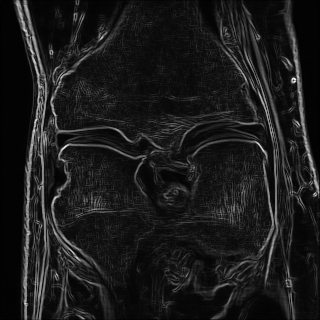

Edge preserving has always been a crucial concern in the design of reconstruction models. To improve the quality of reconstructed images and preserve image edges, some works suggested introducing edge priors in the original restoration problem to preserve image edges [4, 34]. However, they will suffer from complicated algorithm design and time-consuming training processes. Recently, some more efficient methods have been proposed to use edge maps as external guidance for image restoration. For example, Yang et al. [48] used off-the-shelf edge detectors to extract image edges from the degraded images. Fang et al. [12] predicted image edges by constructing an edge reconstruction network. Huang et al. [18] designed a novel dual discriminator GAN framework for solving fast multi-channel MRI, in which one GAN network is built for edge information enhancement. Inspired by these methods, we also consider introducing image edge prior as external guidance to MRI reconstruction since 1) image edges are prominent and distinguishable features in MRI (see Fig. 1), which can serve as a good guide to the model to recover high-frequency details; 2) the ground truth edges can be easily fetched via ordinary edge extraction operators, like Canny, Sobel, and Prewitt, which means that the edge maps can be learned in a data-driven manner. However, how to effectively utilize image edge priors to guide image reconstruction still remains a challenge. In some methods, edge information was simply concatenated with the input image and passed to the next stages. Though this is a simple way to utilize the edge priors, it may not give full play to the guiding role of the edge priors. Therefore, in this work, we want to explore a more efficient and effective mechanism to fully take advantage of image edge priors.

(a)

(b)

(c)

fastMRI is a large-scale MR dataset jointly established by Facebook AI Research and NYU Langone Health. It provides both knee and brain datasets for evaluation. In our work, we use the multi-coil knee dataset, which was acquired on three clinical 3T systems or one clinical 1.5T system using a 15-channel knee coil array. The dataset includes data from two pulse sequences, yielding coronal proton-density weighting with (PDFS) and without (PD) fat suppression. As is shown in Fig. 1, PD images usually contain more structural and prominent edge features than PDFS images, which suggests that it is more challenging to use edge guidance on PDFS datasets. Therefore, we explore the effectiveness of EAMRI on these two modalities. Following [13], for both PD and PDFS knee datasets, we separately filter out 227 volumes (8332 slices) for training and 24 volumes (1665 slices) for testing. The dataset is centrally cropped to .